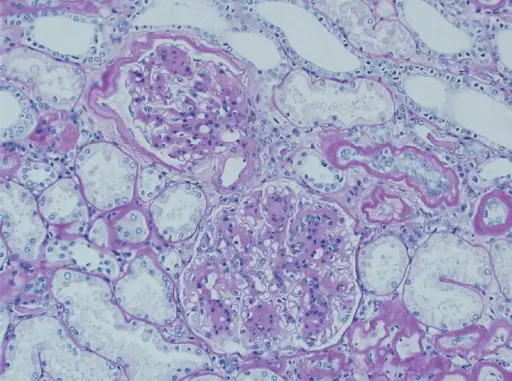

Arteriolosclerosis

Arteriolosclerosis results in small arteriole narrowing.

Arteriolosclerosis is categorized as hyaline and hyperplastic varieties.

Protein leakage into the arterial wall, which results in vascular thickening, is the primary cause of hyaline arteriolosclerosis.

On microscopy arteriosclerosis appears as pink hyaline around the circumference of the vessel.

Risk factors for arteriolosclerosis include:

- Hypertension

- Diabetes

Arteriolosclerosis may results in end-organ ischemia and reduced vascular diameter such as causes glomerular scarring (arteriolonephrosclerosis), which advances gradually to chronic renal failure.

Hyperplastic arteriolosclerosis thickens the artery wall by causing smooth muscle hyperplasia in an “onion-skin” pattern.

Fibrinoid necrosis of the vessel wall may also be seen in hyperplastic arteriolosclerosis.

Malignant hypertension may be related to hyperplastic arteriosclerosis due to rapid decreased vessel diameter.

Arteriolosclerosis may cause acute renal failure, and has a distinctive “flea-bitten” appearance.